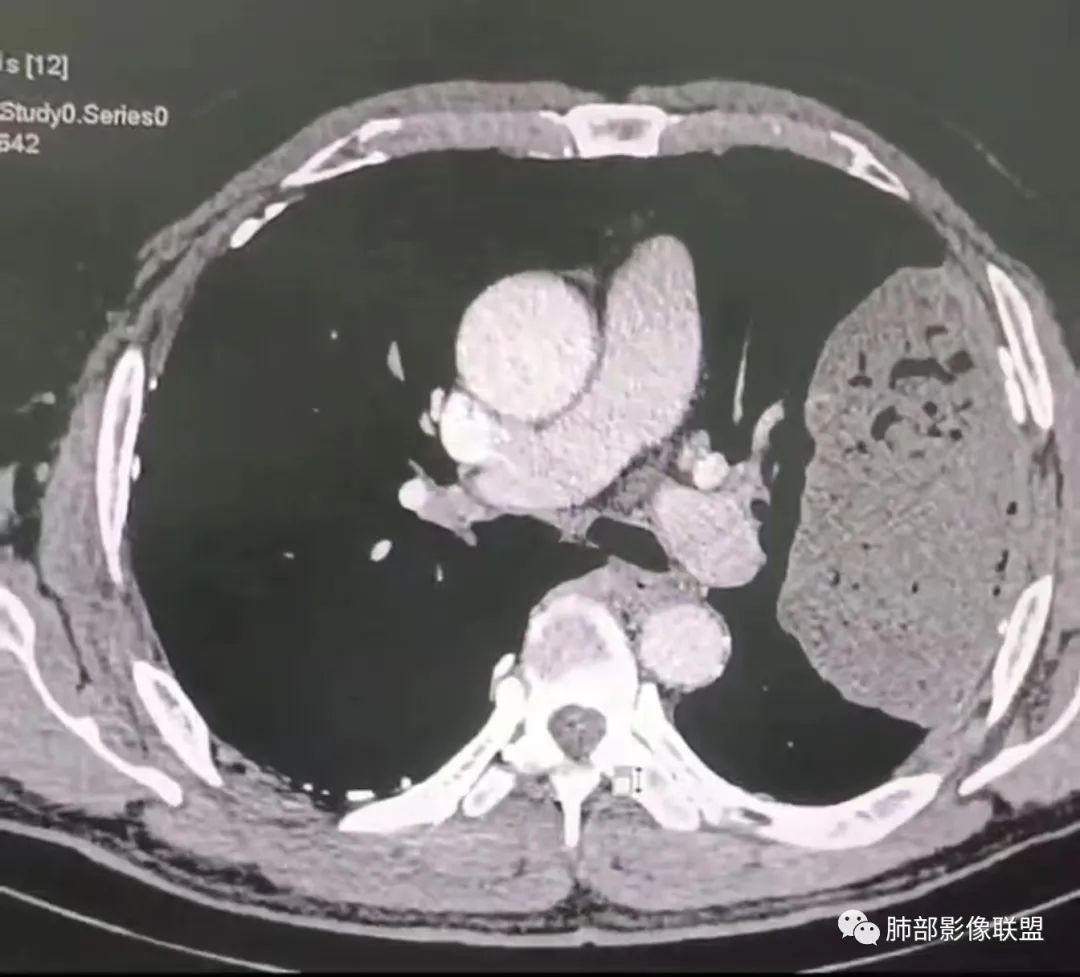

左肺上叶大肿块,膨胀性生长,边界清,密度较低,见部分坏死区,强化弱,肿块见支气管充气V扩张征,分布僵直,枯树枝特点,另一个重要特点血管造影征,淋巴瘤,肿块长轴与胸膜平行,与隐球菌鉴别,隐球荚膜抗原检查,明确诊断经皮肺穿刺。另胸膜钙化(问诊既往有无患胸膜炎病史)。

左肺上叶胸膜下肿块,宽基底与胸膜相连,跨叶裂,边缘清晰膨隆,其内支气管充气,部分扩张、僵直,无明显强化,血管造影征,考虑淋巴瘤,鉴别腺癌

左肺胸膜下巨大占位,跨叶裂,宽基底与胸膜相连,胸膜钙化,平扫密度较低,强化不明显,可见内部血管显影,支气管充气征和扩张,考虑为恶性,倾向于淋巴瘤

支持淋巴瘤,左上肺大肿块,有分叶,边缘光整,病灶内密度不均,可见支气管扩张征,增强后可见血管影征。周围肺野清晰。

左肺上叶肿块,宽基底与胸膜相连,跨叶裂,边缘清晰膨隆,可见小分叶,其内支气管充气,部分扩张、僵直,呈枯枝征,支气管达边征,增强无明显强化,可见血管造影征,考虑恶性病变,淋巴瘤,鉴别粘液腺癌。

大肿块,边缘光滑,深分叶

近端支气管堵塞、推移为主

部分类似于脐凹征

内部支气管扩张

肺动脉推移为主,边缘部分进入

1)部位:周围型或中央型软组织肿块,以周围型为多见,且肿瘤多位于肺上叶。如本例:该肿瘤位于左肺上叶。

2)大小及形态:由于本病恶性程度高,早期症状不明显,发现时肿块均较大。如本例病变巨大。

3)肿块边界和边缘:多较清楚,呈圆形、类圆形,且由于肿块生长速度不均匀,可见分叶,毛刺少见。有报道肿块周围毛玻璃影是多形性癌特征表现。

4)密度:肿块平扫为软组织密度,由于体积较大,内部常见大片状坏死,可出现不规则厚壁空洞或坏死内多发无壁小空洞,坏死多不均匀:坏死灶内可见如柳絮样的斑片样强化灶,坏死边缘与非坏死区分界不清本例坏死较明显,密度不均匀。

5)肿瘤强化方式:肺部恶性肿瘤强化程度与其血供丰富程度相关,血供丰富多强化明显,反之则较差。由于PSC 周边实性部分富血供及内部黏液变性、坏死,增强后肿块多数呈轻-中度边缘环形强化或不均匀小斑片状强化。国外学者对照病理发现肿瘤细胞或胶原组织增强扫描时强化,无强化的低密度区代表了黏液样变性区和出血坏死区。